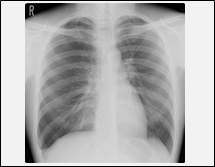

| 訪問レントゲン撮影により、次のような撮影が可能になります。 |

肺炎または肺炎疑い

咳が続くなど肺炎が疑われる際に、確認のための撮影が可能になります。 |

本サービスを利用することで介護施設内での胸部のレントゲン撮影が可能となります。

これまでは胸部レントゲン撮影のためだけに病院・クリニックまで搬送していましたが、今後はその必要がなくなります。患者さまにとっては身体的・経済的負担が軽くなり、介護施設さまにとっては搬送や付き添いを行う手間が軽減されます。主治医の先生方にとりましても、レントゲン撮影を除く健康診断項目をご自身の医療機関で行うことが可能になり、患者さまの健康管理がより一層行いやすくなります。 |